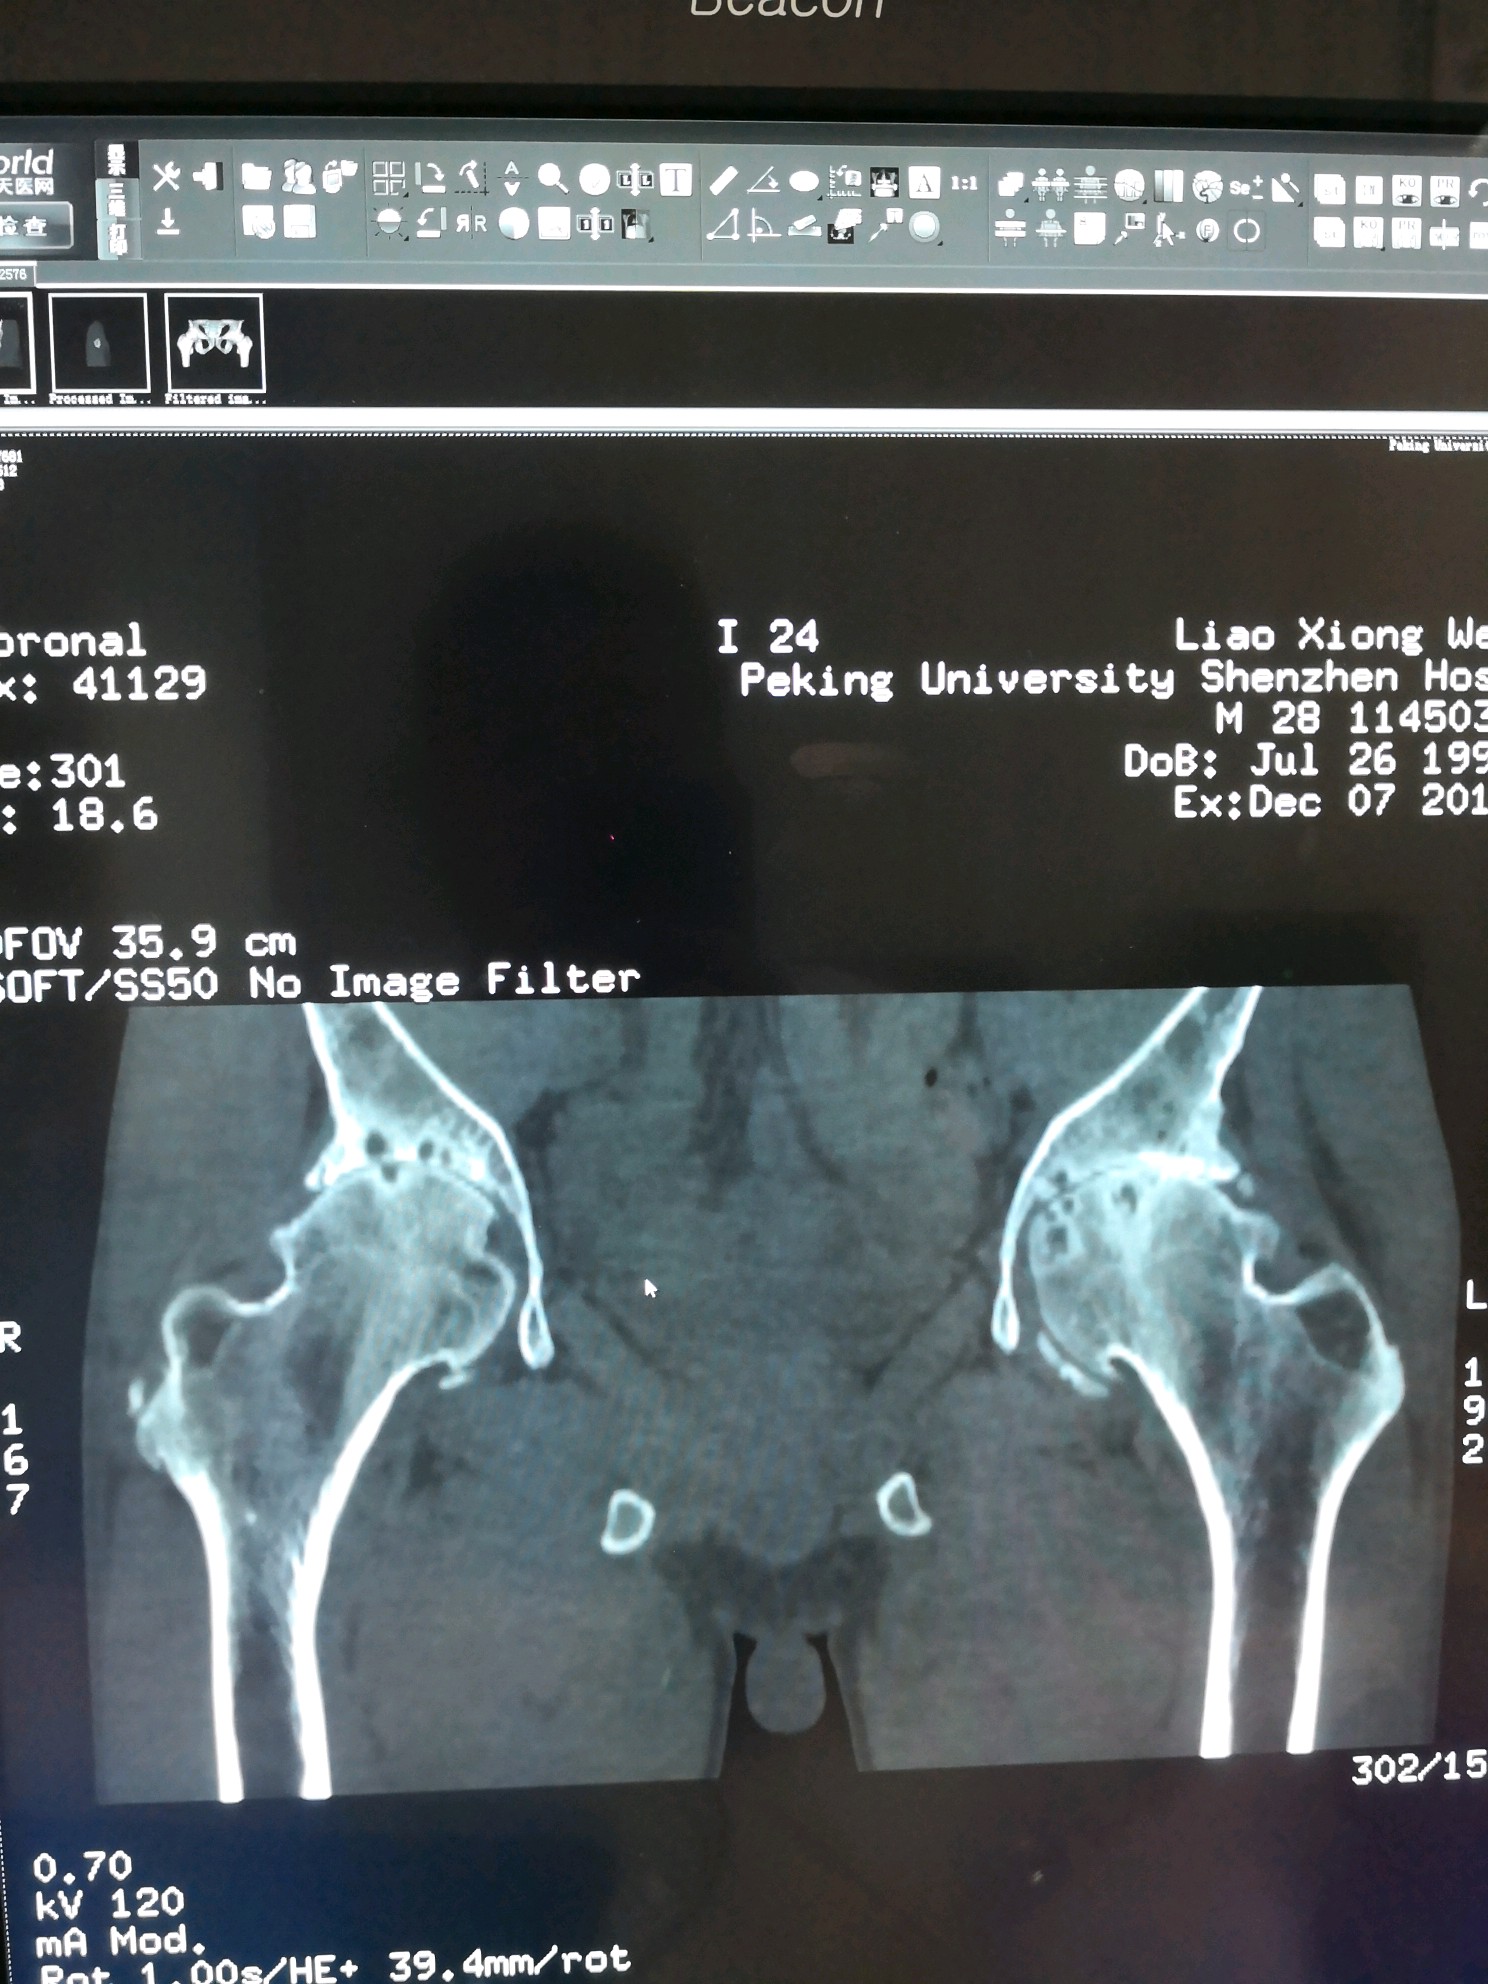

术前双髋CT片

图片发自160医生App